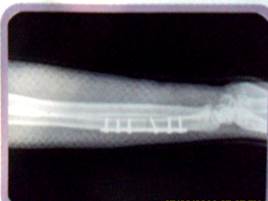

Висока рентгенівська прозорість

Завдяки рентгенівській прозорості фахівець має можливість у будь-який момент контролювати процес лікування.